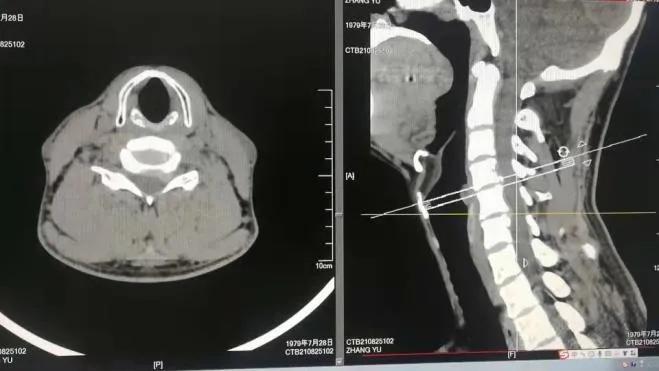

患者是一名年轻男性,一年多来,常伴有左上肢麻木不适,就在一个月前,患者在进行理疗治疗时症状加重,出现头部不能屈曲及过伸,左上肢麻木明显,夜不能眠,令他痛苦不堪。入住我院龙湾院区脊柱关节外科后,经检查发现颈椎间盘突出,神经根受压明显。

经过脊柱关节外科中心会诊,诊断患者为神经根型颈椎病,根据患者的典型症状,医生建议行微创颈椎后路椎间孔切开术KEY-hole(钥匙孔技术)。在脊柱关节外科中心手术团队的共同努力下,手术过程顺利,术后患者恢复良好。